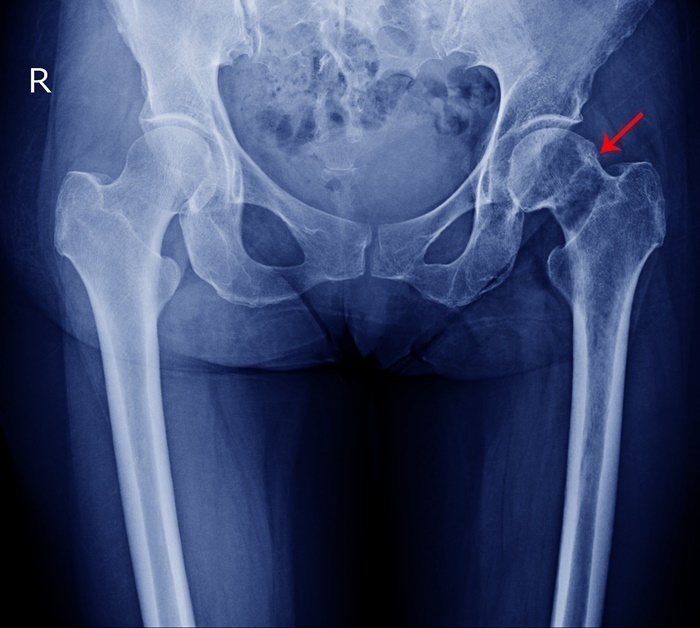

위키트리단순한 근육통이라 여겼지만, 검진 결과 그는 ‘대퇴골두 무혈성 괴사’ 진단을 받았다. 골반 괴사라고도 불리는 이 질환은 대퇴골의 머리 부분으로 가는 혈액 공급이 차단되면서 뼈 조직이 서서히 괴사하는 질병이다.

진단을 위해서는 엑스레이와 MRI 촬영이 필요하다. 초기 단계에서는 엑스레이에서 이상이 보이지 않을 수 있으므로, 보다 정밀한 검사가 요구된다. 치료 방법은 병의 진행 정도에 따라 달라진다. 초기라면 약물 치료와 혈류 개선을 위한 물리치료, 체중 조절 등이 권장된다. 하지만 괴사가 심해지면 뼈 이식술이나 인공관절 치환술이 필요할 수도 있다.